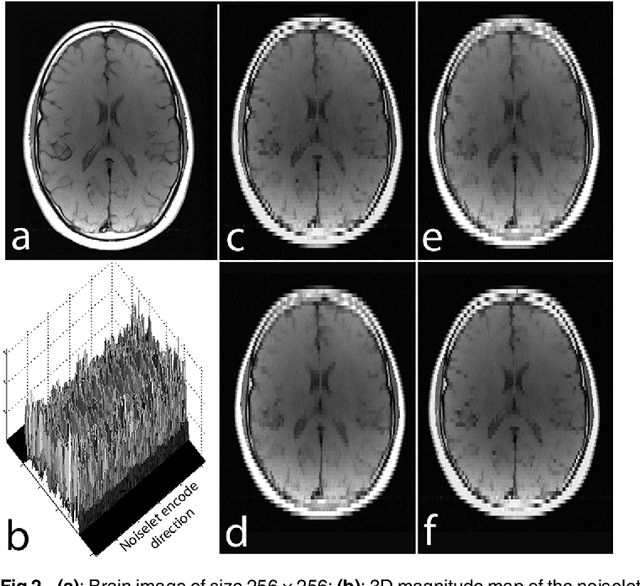

Abstract:The incoherence between measurement and sparsifying transform matrices and the restricted isometry property (RIP) of measurement matrix are two of the key factors in determining the performance of compressive sensing (CS). In CS-MRI, the randomly under-sampled Fourier matrix is used as the measurement matrix and the wavelet transform is usually used as sparsifying transform matrix. However, the incoherence between the randomly under-sampled Fourier matrix and the wavelet matrix is not optimal, which can deteriorate the performance of CS-MRI. Using the mathematical result that noiselets are maximally incoherent with wavelets, this paper introduces the noiselet unitary bases as the measurement matrix to improve the incoherence and RIP in CS-MRI, and presents a method to design the pulse sequence for the noiselet encoding. This novel encoding scheme is combined with the multichannel compressive sensing (MCS) framework to take the advantage of multichannel data acquisition used in MRI scanners. An empirical RIP analysis is presented to compare the multichannel noiselet and multichannel Fourier measurement matrices in MCS. Simulations are presented in the MCS framework to compare the performance of noiselet encoding reconstructions and Fourier encoding reconstructions at different acceleration factors. The comparisons indicate that multichannel noiselet measurement matrix has better RIP than that of its Fourier counterpart, and that noiselet encoded MCS-MRI outperforms Fourier encoded MCS-MRI in preserving image resolution and can achieve higher acceleration factors. To demonstrate the feasibility of the proposed noiselet encoding scheme, two pulse sequences with tailored spatially selective RF excitation pulses was designed and implemented on a 3T scanner to acquire the data in the noiselet domain from a phantom and a human brain.